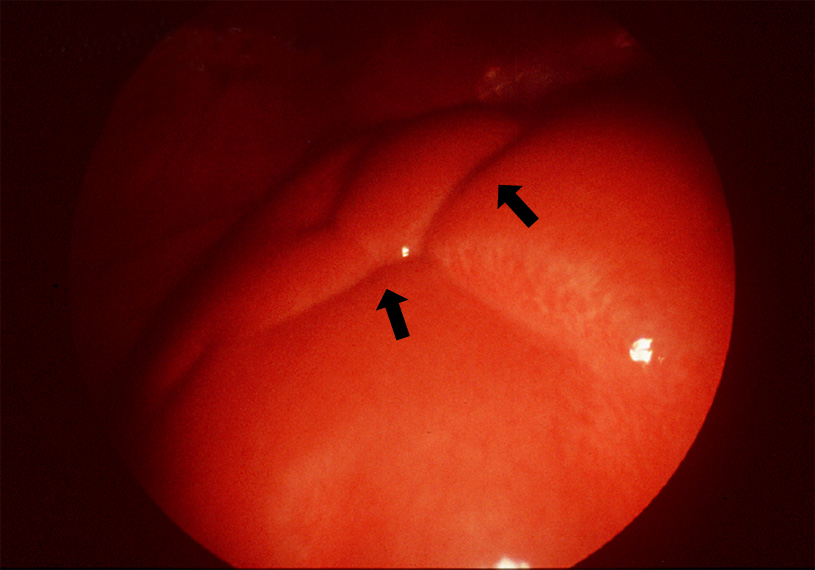

自己免疫性肝炎(急性期、腹腔鏡所見)

溝状陥凹をみる。症例1([ID0509])の所見である。